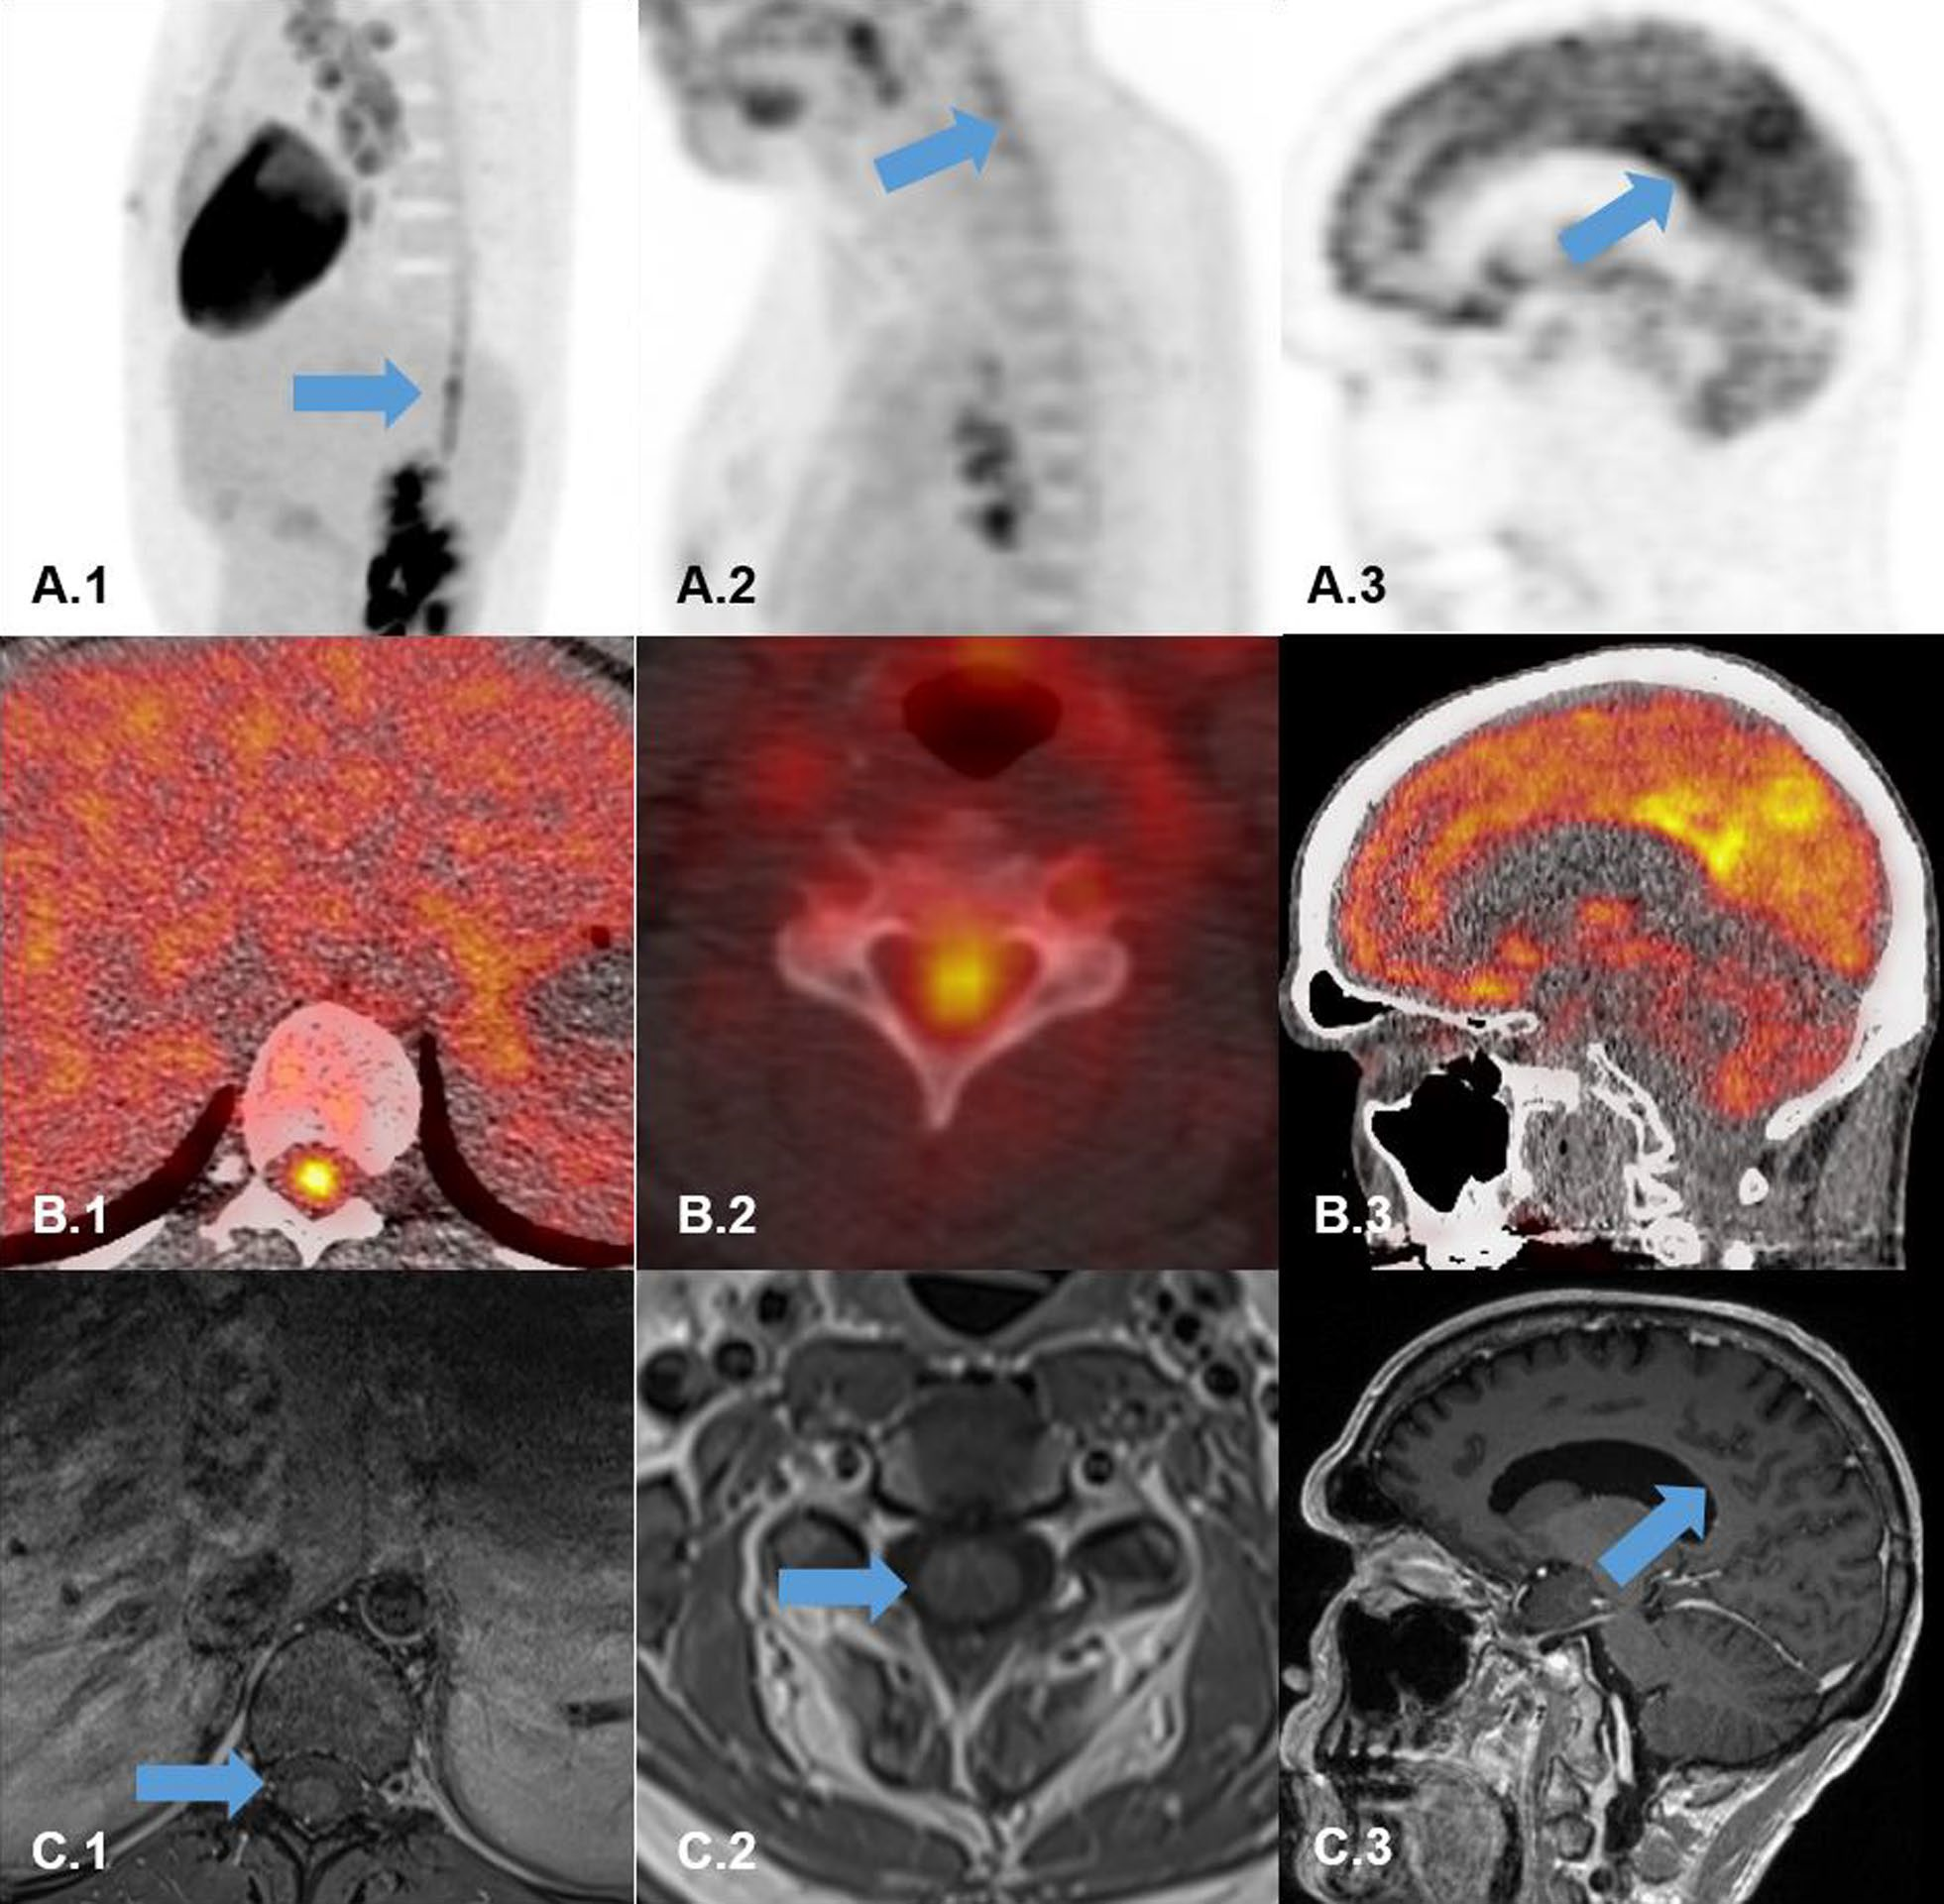

Data analysis validation. Panel A: Image and line profile through the bottle on scans 1 (top) and 2 (middle), and the difference image (bottom) calculated according to Equation 3. Panel B: Data from a representative participant showing the effect of the dose correction on the PETWALK image using Equation 1 when applied to co-registered images in native subject space. The images were then warped to standard Montreal Neurological Institute (MNI) space Top: PETSTAND, middle – uncorrected PETWALK, bottom – corrected PETWALK. The color bar shows image intensity across the three images. Image courtesy of NeuroImage.